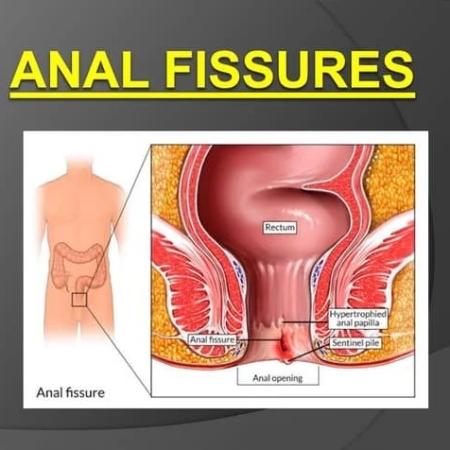

Fissures

Fissures result from the stretching of your anal mucosa beyond its normal capacity. This often happens when stools are hard due to constipation. Once the tear happens, it leads to repeated injury. The exposed internal sphincter muscle beneath the tear goes